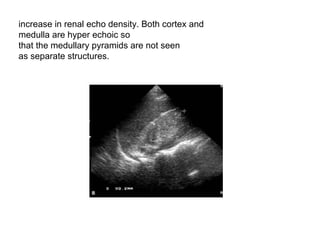

increase in renal echo density. Both cortex and  medulla are hyper echoic so  that the medullary pyramids are not seen  as separate structures.